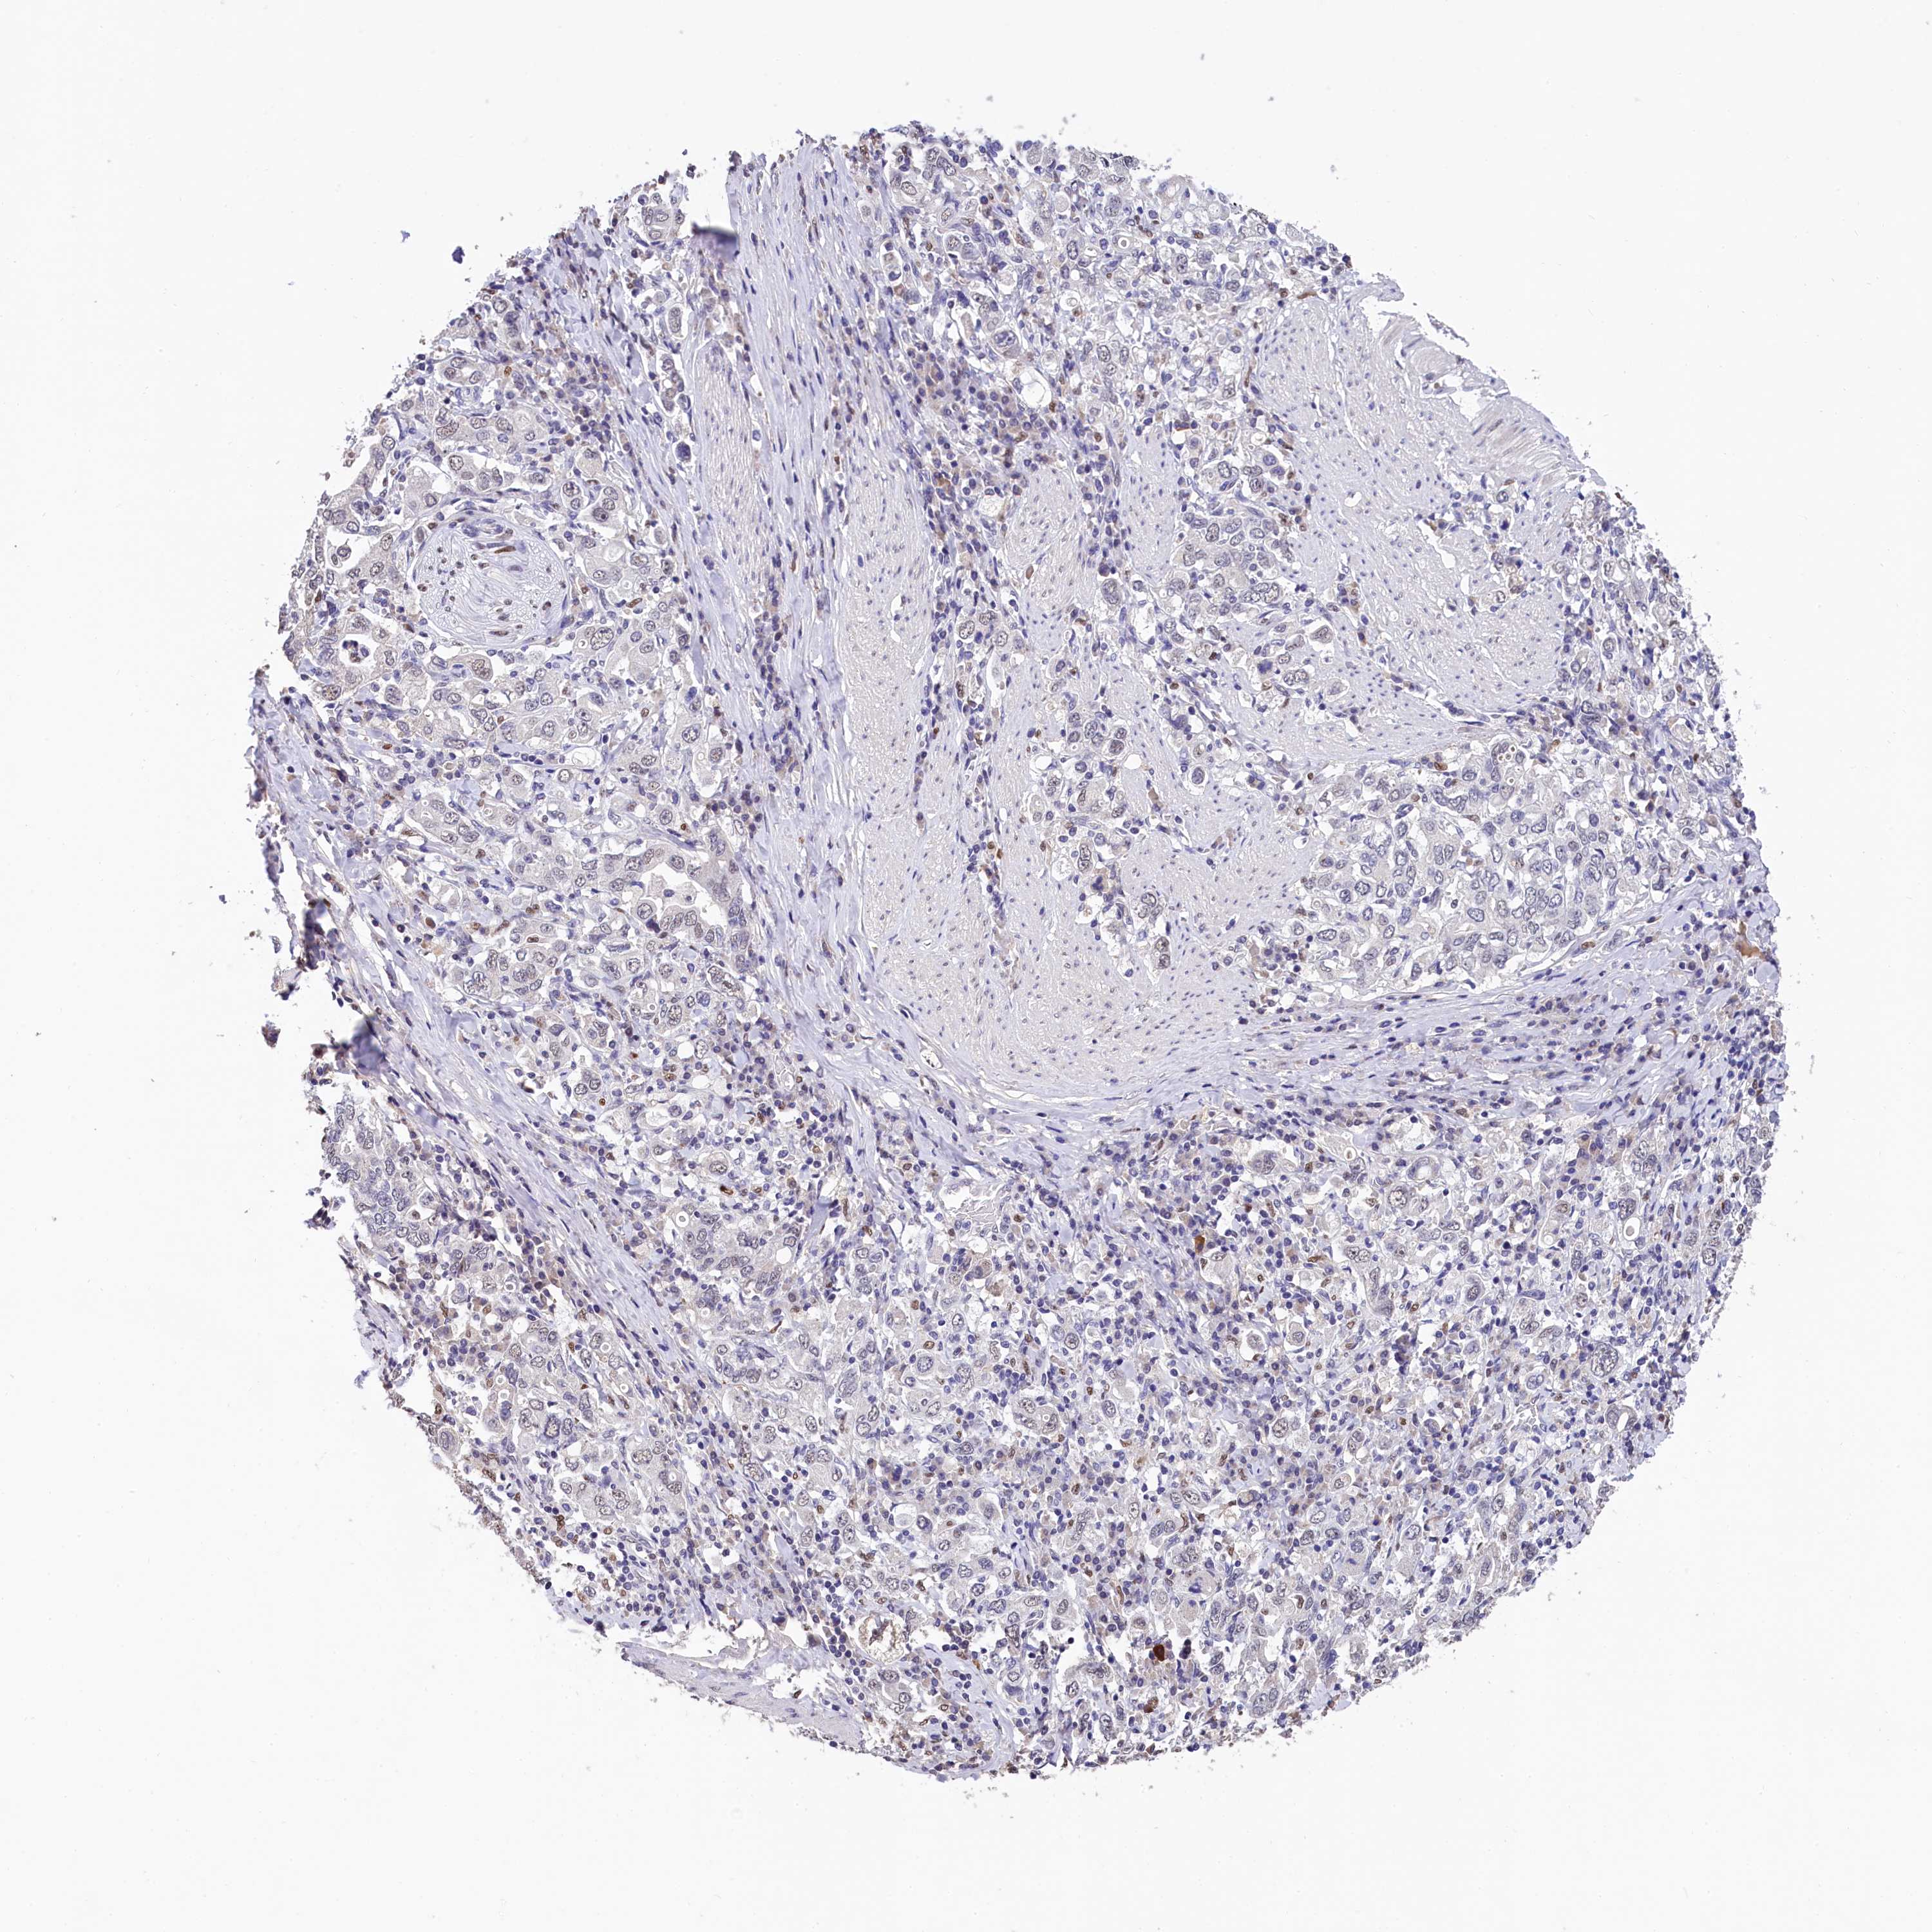

STOMACH CANCER - Protein expressioni

A mouse-over function shows sample information and annotation data. Click on an image to view it in a full screen mode. Samples can be filtered based on level of antibody staining by selecting one or several of the following categories: high, medium, low and not detected. The assay and annotation is described here.

Note that samples used for immunohistochemistry by the Human Protein Atlas do not correspond to samples in the TCGA dataset.

Antibody stainingi

Antibody staining in the annotated cell types in the current human tissue is reported as not detected, low, medium, or high, based on conventional immunohistochemistry profiling in selected tissues. This score is based on the combination of the staining intensity and fraction of stained cells.

Each image is clickable and will lead to virtual microscopy that enables deeper exploration of all samples and also displays staining intensity scores, fraction scores and subcellular localization as well as patient and tissue information for each sample.

Antibody HPA041062

Antibody HPA045473

Staining

High

Medium

Low

Not detected

Intensity

Strong

Moderate

Weak

Negative

Quantity

>75%

75%-25%

<25%

None

Location

Nuclear

Cytoplasmic/membranous

Cytoplasmic/membranous,nuclear

Adenocarcinoma, NOS